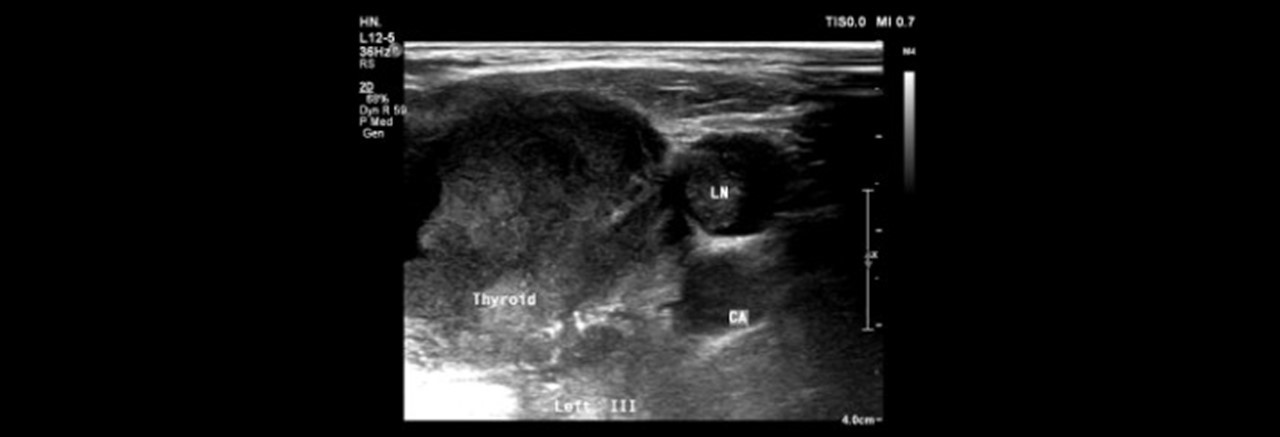

圖一(甲狀腺炎 超音波照  /  佳齡生活健康中心 耳鼻喉科主治醫師 孫強醫師提供 )

圖二(甲狀腺結節 超音波照  /  佳齡生活健康中心 耳鼻喉科主治醫師 孫強醫師提供 )

圖三(甲狀腺癌 超音波照  /  佳齡生活健康中心 耳鼻喉科主治醫師 孫強醫師提供 )